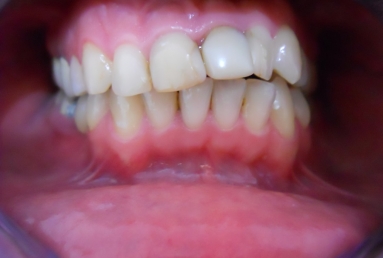

The orthodontic treatment was necessary as the upper maxillary developed assimetricaly, also the teeth were malpositioned. The purpose of the partial braces was to help the final prosthetic treatment, which consisted of two full ceramic crowns for the central incisors, that had root canal treatments, and a ceramic veneer for the lateral incisor, that had a large composite filling. Gingivectomies were also necessary for the right canine and incisors in order to correct the assymetrical gummy smile.